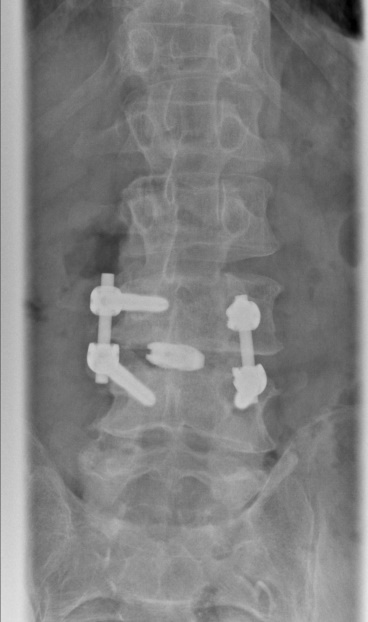

Beispiel Wirbelgleiten

Beim Wirbelgleiten (Spondylolisthese) verschieben sich einzelne Wirbelkörper zueinander. Dies kann durch Abnutzung oder angeborene Verknöcherungsstörungen bedingt sein und sowohl in hohem Alter als auch in der Jugend zu Beschwerden führen. Das Wirbelgleiten kann durch die damit verbundene Instabilität zu Rückenschmerzen oder auch durch Verengungen an Wirbelkanal und Nervenaustrittslöchern zu schmerzhafter Ausstrahlung in die Beine führen. Sollten krankengymnastische Behandlungen oder minimalinvasive Therapiemöglichkeiten, keine Beschwerdelinderung erreichen, so wird in einer Operation zunächst das regelrechte Profil der Wirbelsäule wieder hergestellt und anschließend stabilisiert (Repositionsspondylodese). Die zwischen den Wirbelkörpern liegende Bandscheibe ist in der Regel zerstört und wird durch einen Platzhalter ersetzt. Diese Maßnahme kann von vorne, von der Seite oder von hinten am Wirbelkanal vorbei durchgeführt werden, sie ist wesentlich zur Festigung der Versteifung.